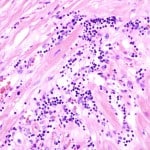

Myocarditis

Introduction Myocarditis is an inflammation of the myocardial layer of heart muscle. Myo=muscle, card=heart, itis=inflammation. The heart wall is made of 3 layers: Endocardium (layer of endothelium & connective tissue lining…